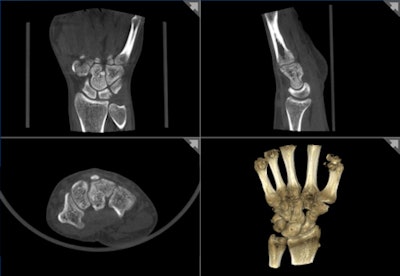

![]() |

| Planmed borrowed conebeam CT technology previously applied to dental imaging for its compact Verity extremity scanner. All images courtesy of Planmed. |

Verity casts a small shadow by employing conebeam CT technology that's widely used in dental radiography, where Planmed plays an important role in equipment design and manufacturing, Tohka said in a telephone interview.